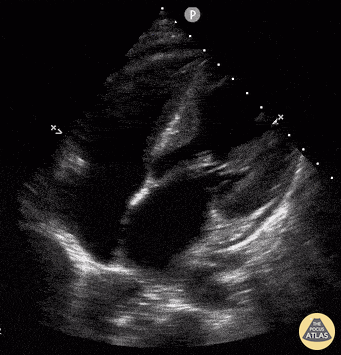

Thoracic Aortic Dissection & Aneurysm - Descending Thoracic Aorta Flap Seen on Apical 4 Chamber

33 yo male presented with chest/epigastric pain. POCUS is notable for acute aortic dissection as seen in the descending thoracic aorta flap as well as presence of a pericardial effusion. Maxime Gautier